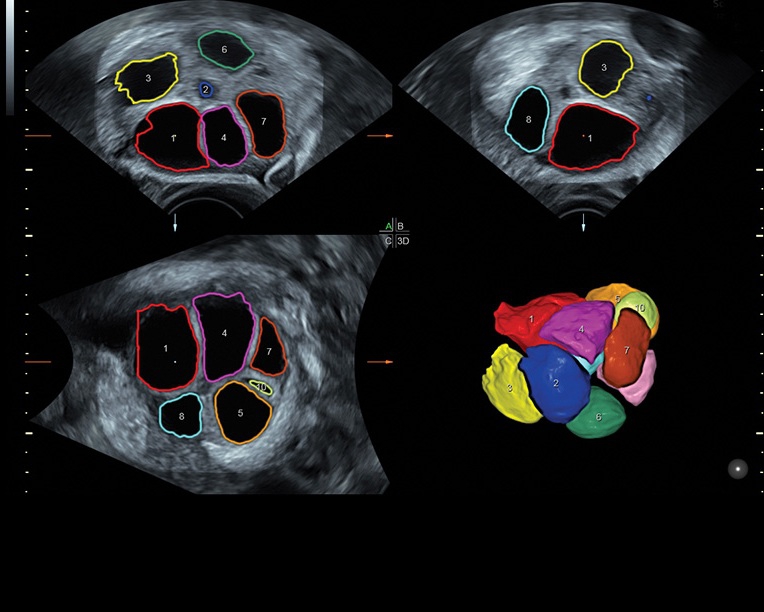

• Сложные инструменты для оценки качества плода: Сканер оснащен инновационными инструментами, позволяющими проводить детальную оценку состояния плода, включая его сердечную деятельность, анатомию и кровоток.

• Программа для исследований сердца плода с возможностью цветовых допплеровских и ангиографических исследований на основе анализа пространственно-временной корреляции изображений (STIС)

• Программное обеспечение для исследования сердца плода в режиме 3D/4D (быстрый доступ к плоскостям сканирования) по рекомендациям ISUOG